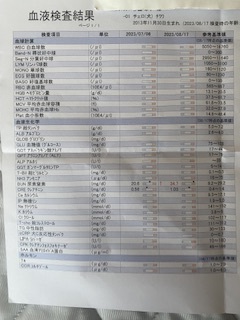

⭐️検査、問診結果⭐️

・普段の様子を細かく聞かれた結果、今飲んでいる薬より心臓のサポートをもっとしてくれる薬に変更する事になりました。

・心エコー

相変わらずの血液検査の逆流

前回と大きく変化はなし

・胸部レントゲン

前回より少し大きくなっている

・血液検査(腎臓の数値)

前回より上がっている

肺水腫になる危険性も高いまま